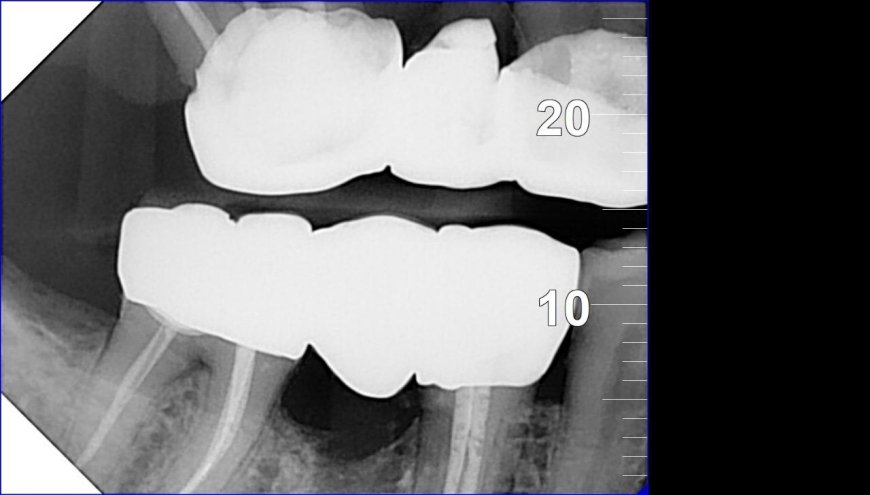

18 الدكتور احمد حسان | أفضل دكتور أسنان في الاردن